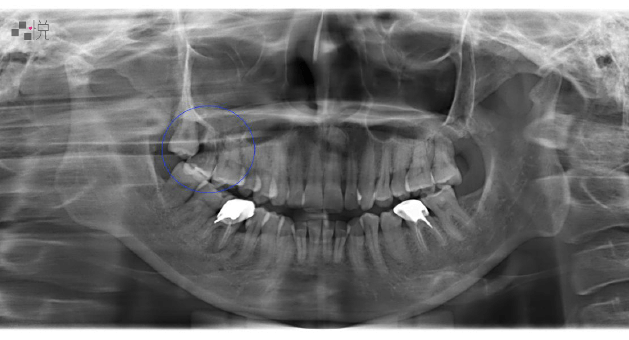

鼻竇炎嚴重蛀牙術前

黃小姐術前 X 光,藍色圈起處為有問題的牙齒。

(案例提供:黃莞婷醫師)